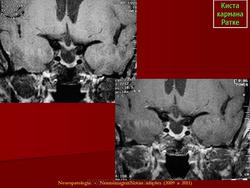

ГМ. Киста кармана Ратке. +

Киста кармана Ратке

Отличные изображения, спасибо. И хорошо что тут стрелочками указана киста и аденогипофиз, который всегда деформирован кистой и киста непосредственно к нему прилижет.